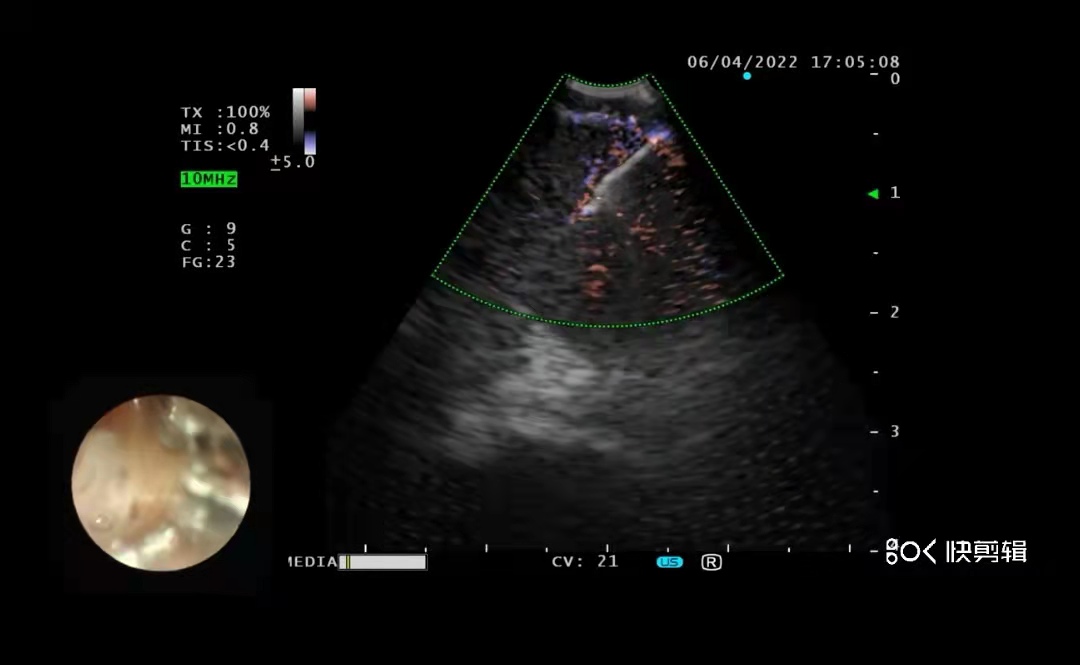

近期,阜阳市第二人民医院引进国内最先进的超声支气管镜(BF-UC290F)并已正式投入使用。

4月6日下午,在市第二人民医院麻醉科和护理团队的配合下,使用新设备BF-UC290F顺利完成第一台经支气管镜超声穿刺手术,经支气管镜超声穿刺技术(EBUS-TBNA)具有微创、安全、可重复操作的特点,可以对纵膈和气管腔外病灶进行诊断、肿瘤分期和治疗。该设备的引进和经超声支气管镜穿刺技术的顺利开展填补了市第二人民医院在超声支气管镜检查的空白,同时可以更好地服务于阜阳地区肺部疾病患者,促进呼吸介入技术更好、更快发展。

超声支气管镜(EBUS)是一种在支气管镜前端安装超声探头的设备,相当于在支气管里面做B超。支气管腔内超声具有创伤小、定位准确、操作性强的特点,可清楚地看到支气管腔外周围4厘米范围的病灶,显示出气道外纵隔内血管、淋巴结与占位性病变的关系,解决了传统气管镜穿刺只能进行“盲穿”的弊端,大大提高了穿刺的准确率和安全性,有效避免了对周围大血管的损伤,降低了手术风险。主要用于以下几种适应症:原因不明的肺门/纵隔淋巴结肿大的诊断;原发性肺癌的肺门/纵隔淋巴结评估;肺内转移性肿瘤的肺门/纵隔淋巴结评估;鉴别纵隔肿瘤和气管支气管原发肿瘤的管壁浸润;探测气道黏膜下病变;判断食道癌有无侵犯气管、支气管。